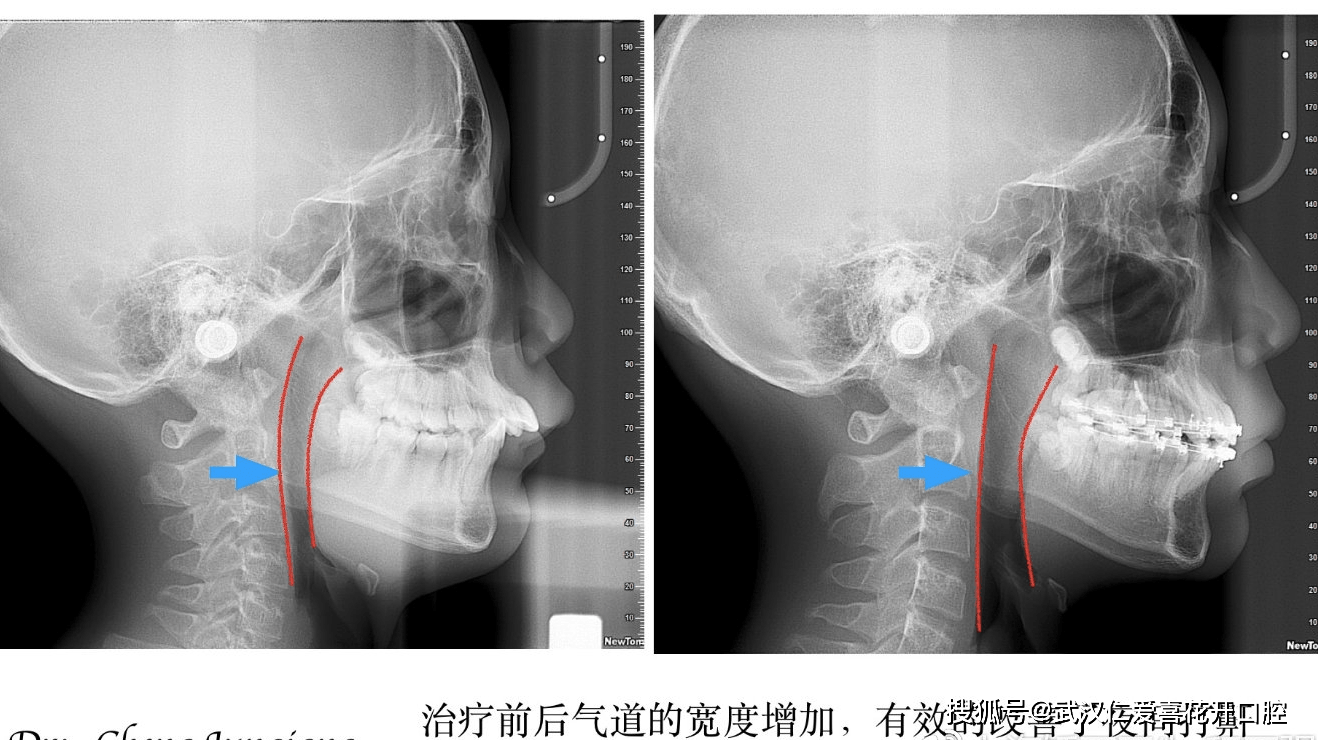

01 关于案例

不可忽视的口腔正畸前常规tmj影像筛查

仁爱口腔严重突面畸形的矫形治疗

图片尺寸1318x740